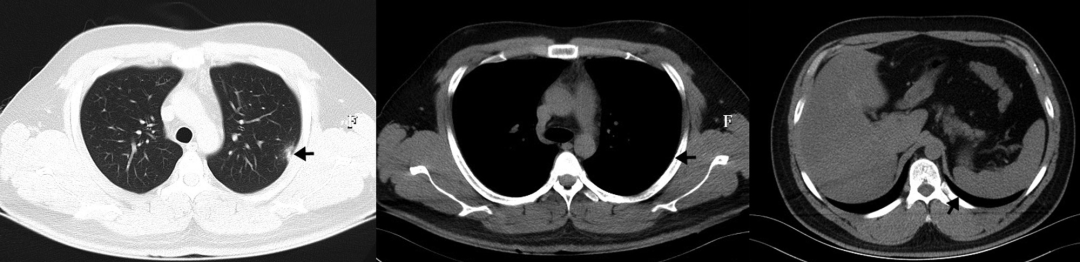

• 第12天,患者临床症状有所缓解,肺部CT较之前明显改善(图5)

图5:第12天,肺部CT示双肺多发感染,较前好转,略弥漫,伴磨玻璃样高密度影